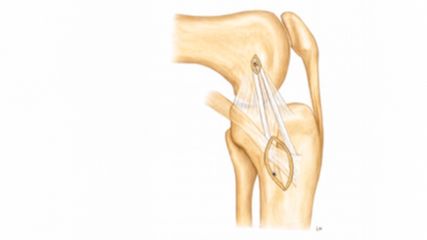

To improve visualization of the central joint cavity during MR arthrography, axial leg traction can be applied, similar to the joint distraction needed during hip arthroscopy (Fig. 1). Traction MR arthrography of the hip has shown high accuracy in detecting chondrolabral lesions, ligamentum teres injuries, and intra-articular loose bodies and has demonstrated its value in predicting failure of FAI surgery.5–8 It is particularly helpful for better visualizing the extent of cartilage damage in older patients with mild radiographic joint degeneration and thus aid in surgical decision making. Traction MR arthrography can also detect unstable labral tears in patients with hip dysplasia and may aid in planning treatment for femoral head necrosis in young patients with early collapse and preserved joint space.4